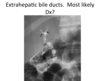

Sclerosing Cholangitis

Extrahepatic ducts –> beaded appearance

Assoc w/ ulcerative cholitis